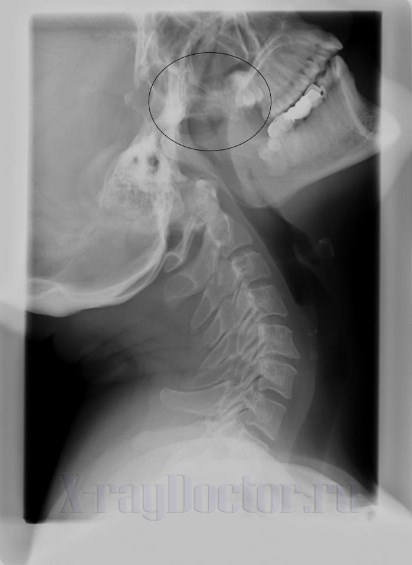

Рентген-диагностика аденоидов у детей при 3-й степени увеличения глоточных миндалин показывает лишь общее увеличение тканей носоглотки. Информативность обследования низкая, поэтому оно практически не применяется.

- При второй степени увеличенные миндалины занимают 1/2 часть носоглотки. Во сне у ребенка наблюдается храп. Разговор малыша становится непонятным. Рентген на данной стадии позволяет выявить увеличенные миндалины.

- Миндалины занимают весь просвет носоглотки. Состояние мешает дышать носом или разговаривать. Клинически данное состояние сопровождается снижением слуха и обоняния. Врачи при 3-й стадии заболевания рекомендуют оперативное лечение.

Гной на снимках визуализируется как светлые пятна. Они исчезают при лечении болезни и контролируются на динамических рентгенограммах. В носоглотке мешки на рентгенограммах прослеживаются в виде белых затемнений. При их обнаружении врачи назначают антибактериальные препараты. При 3-й степени увеличения глоточных миндалин показана операция.